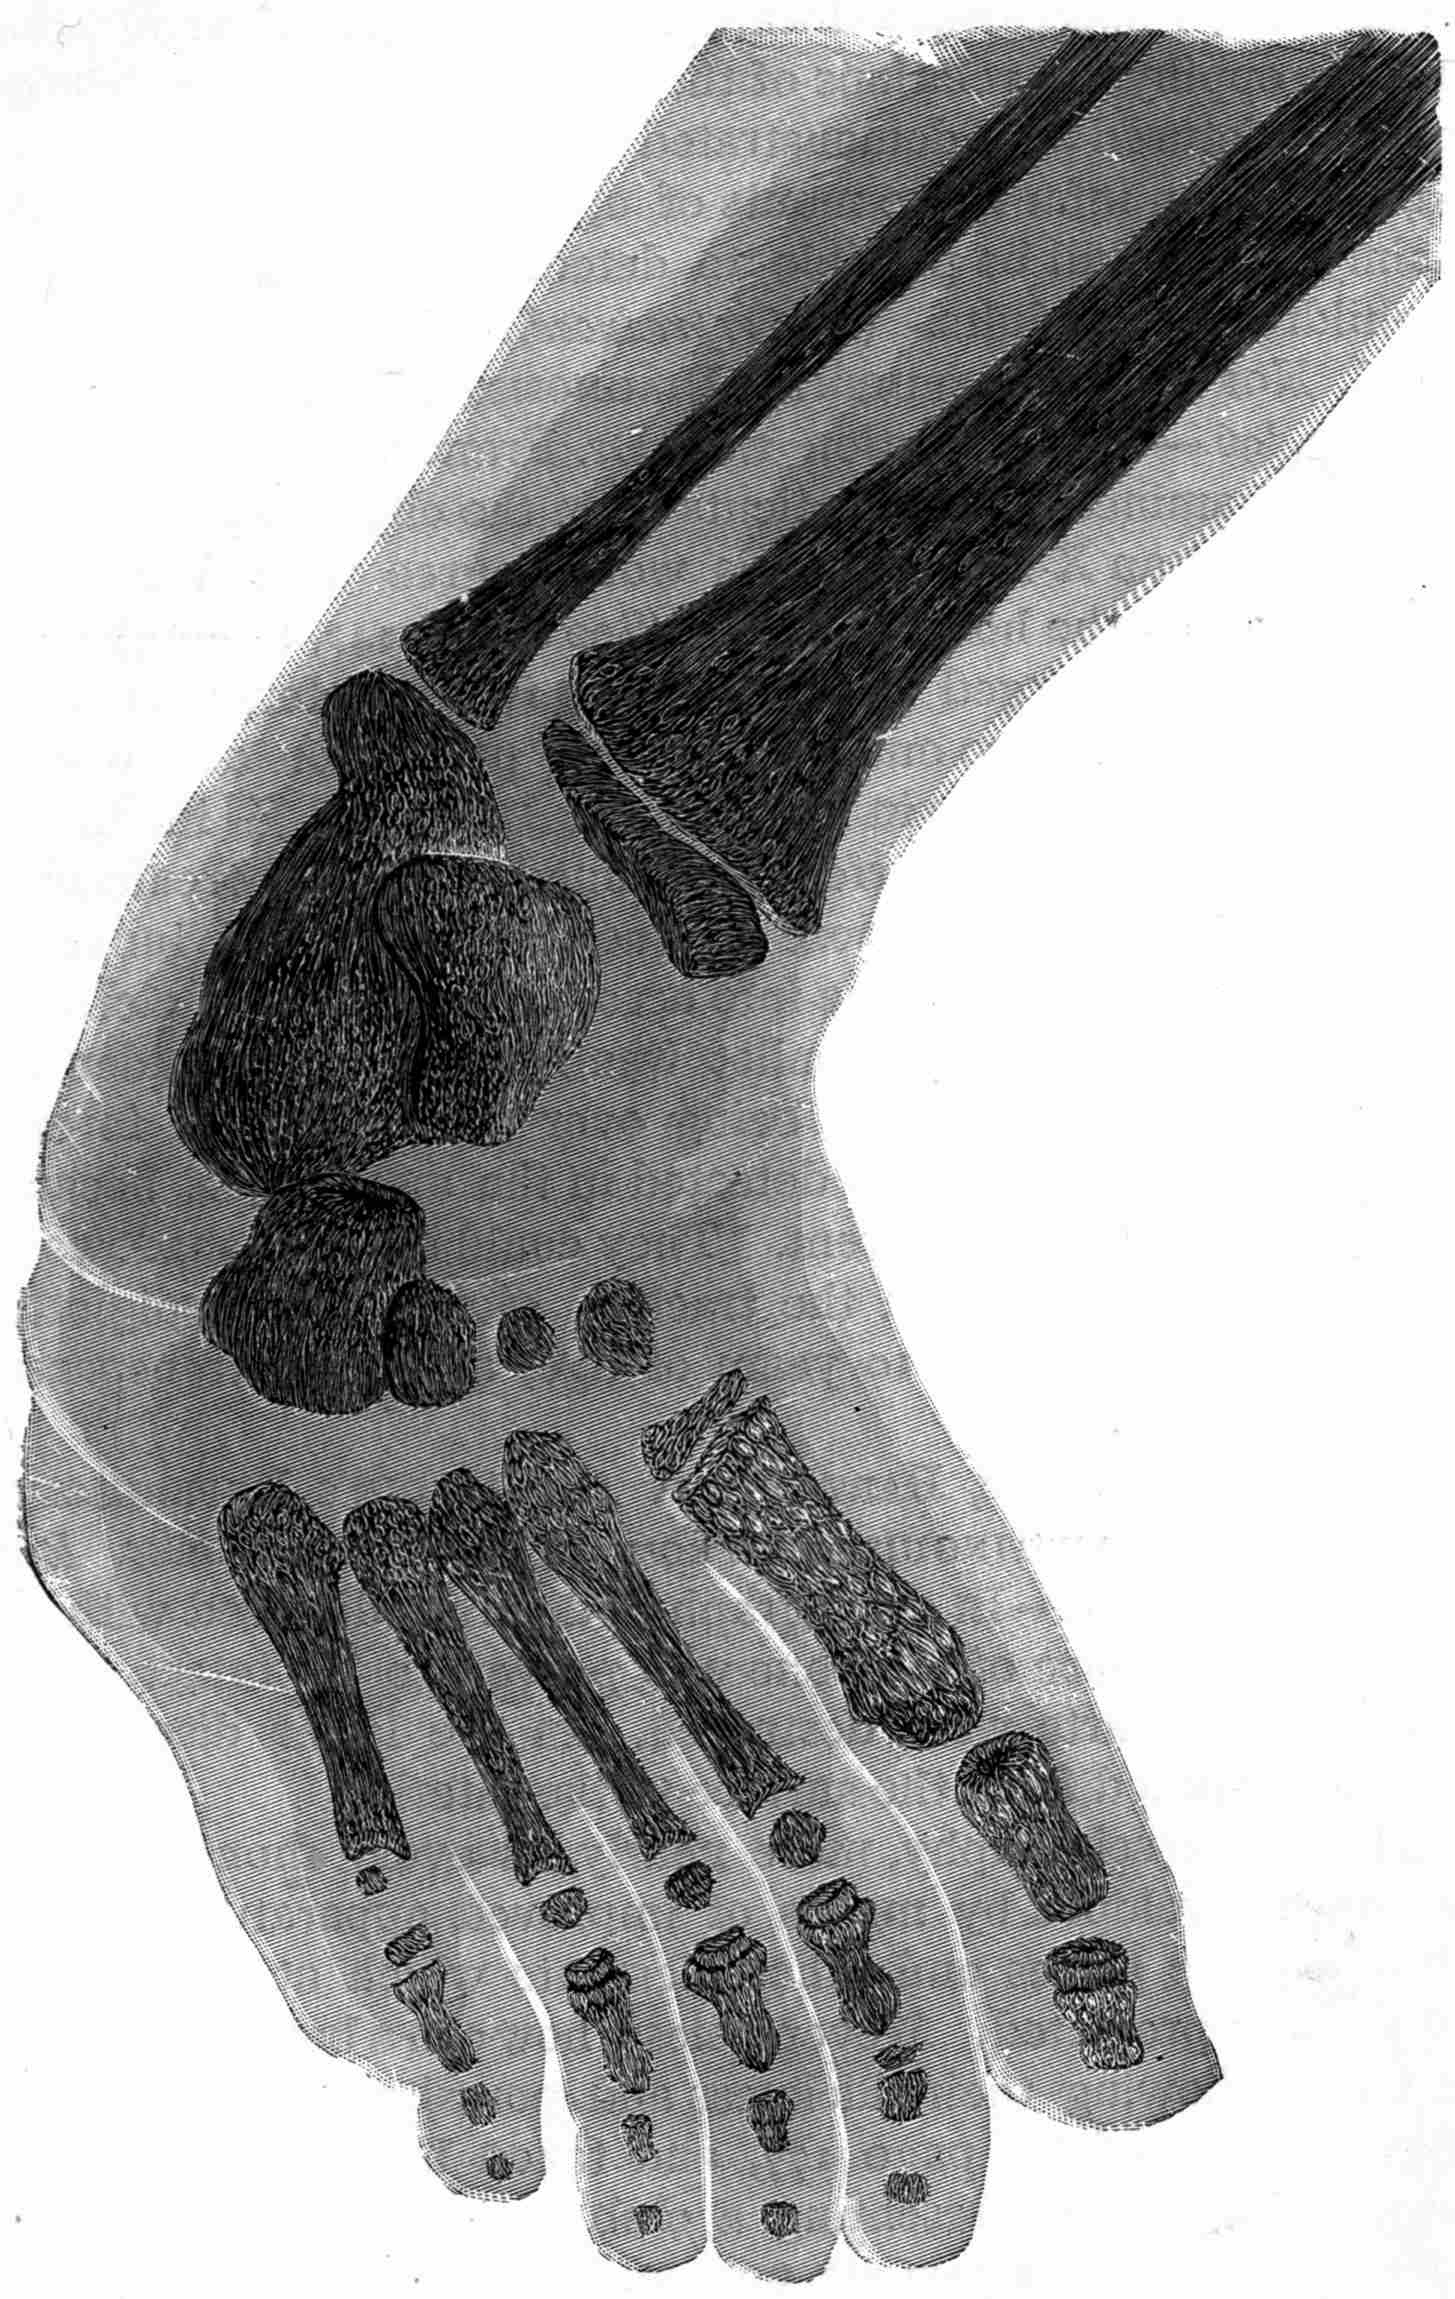

Fig. 2.—Broken Arm, Overlapping.

(Due to defective setting.)

Fig. 3.—Ribs.

Fig. 4.—Knee, Knickerbocker Buttons, Bullet in Femur.

FROM SCIAGRAPHS BY PROF. DAYTON C. MILLER. § 204.